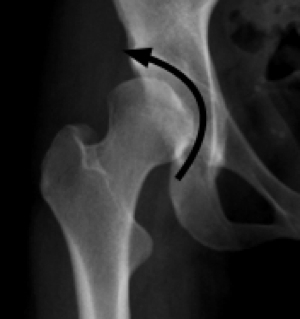

FAIS is found in two forms, one an abnormality of the acetabular rim (Pincer) and the other an abnormality of the femoral neck (CAM).

With Pincer, there is TOO MUCH coverage of the femoral head.

With Developmental Hip Dysplasia, however, there is TOO LITTLE coverage of the femoral head. Consequently the range of motion of the hip is INCREASED.